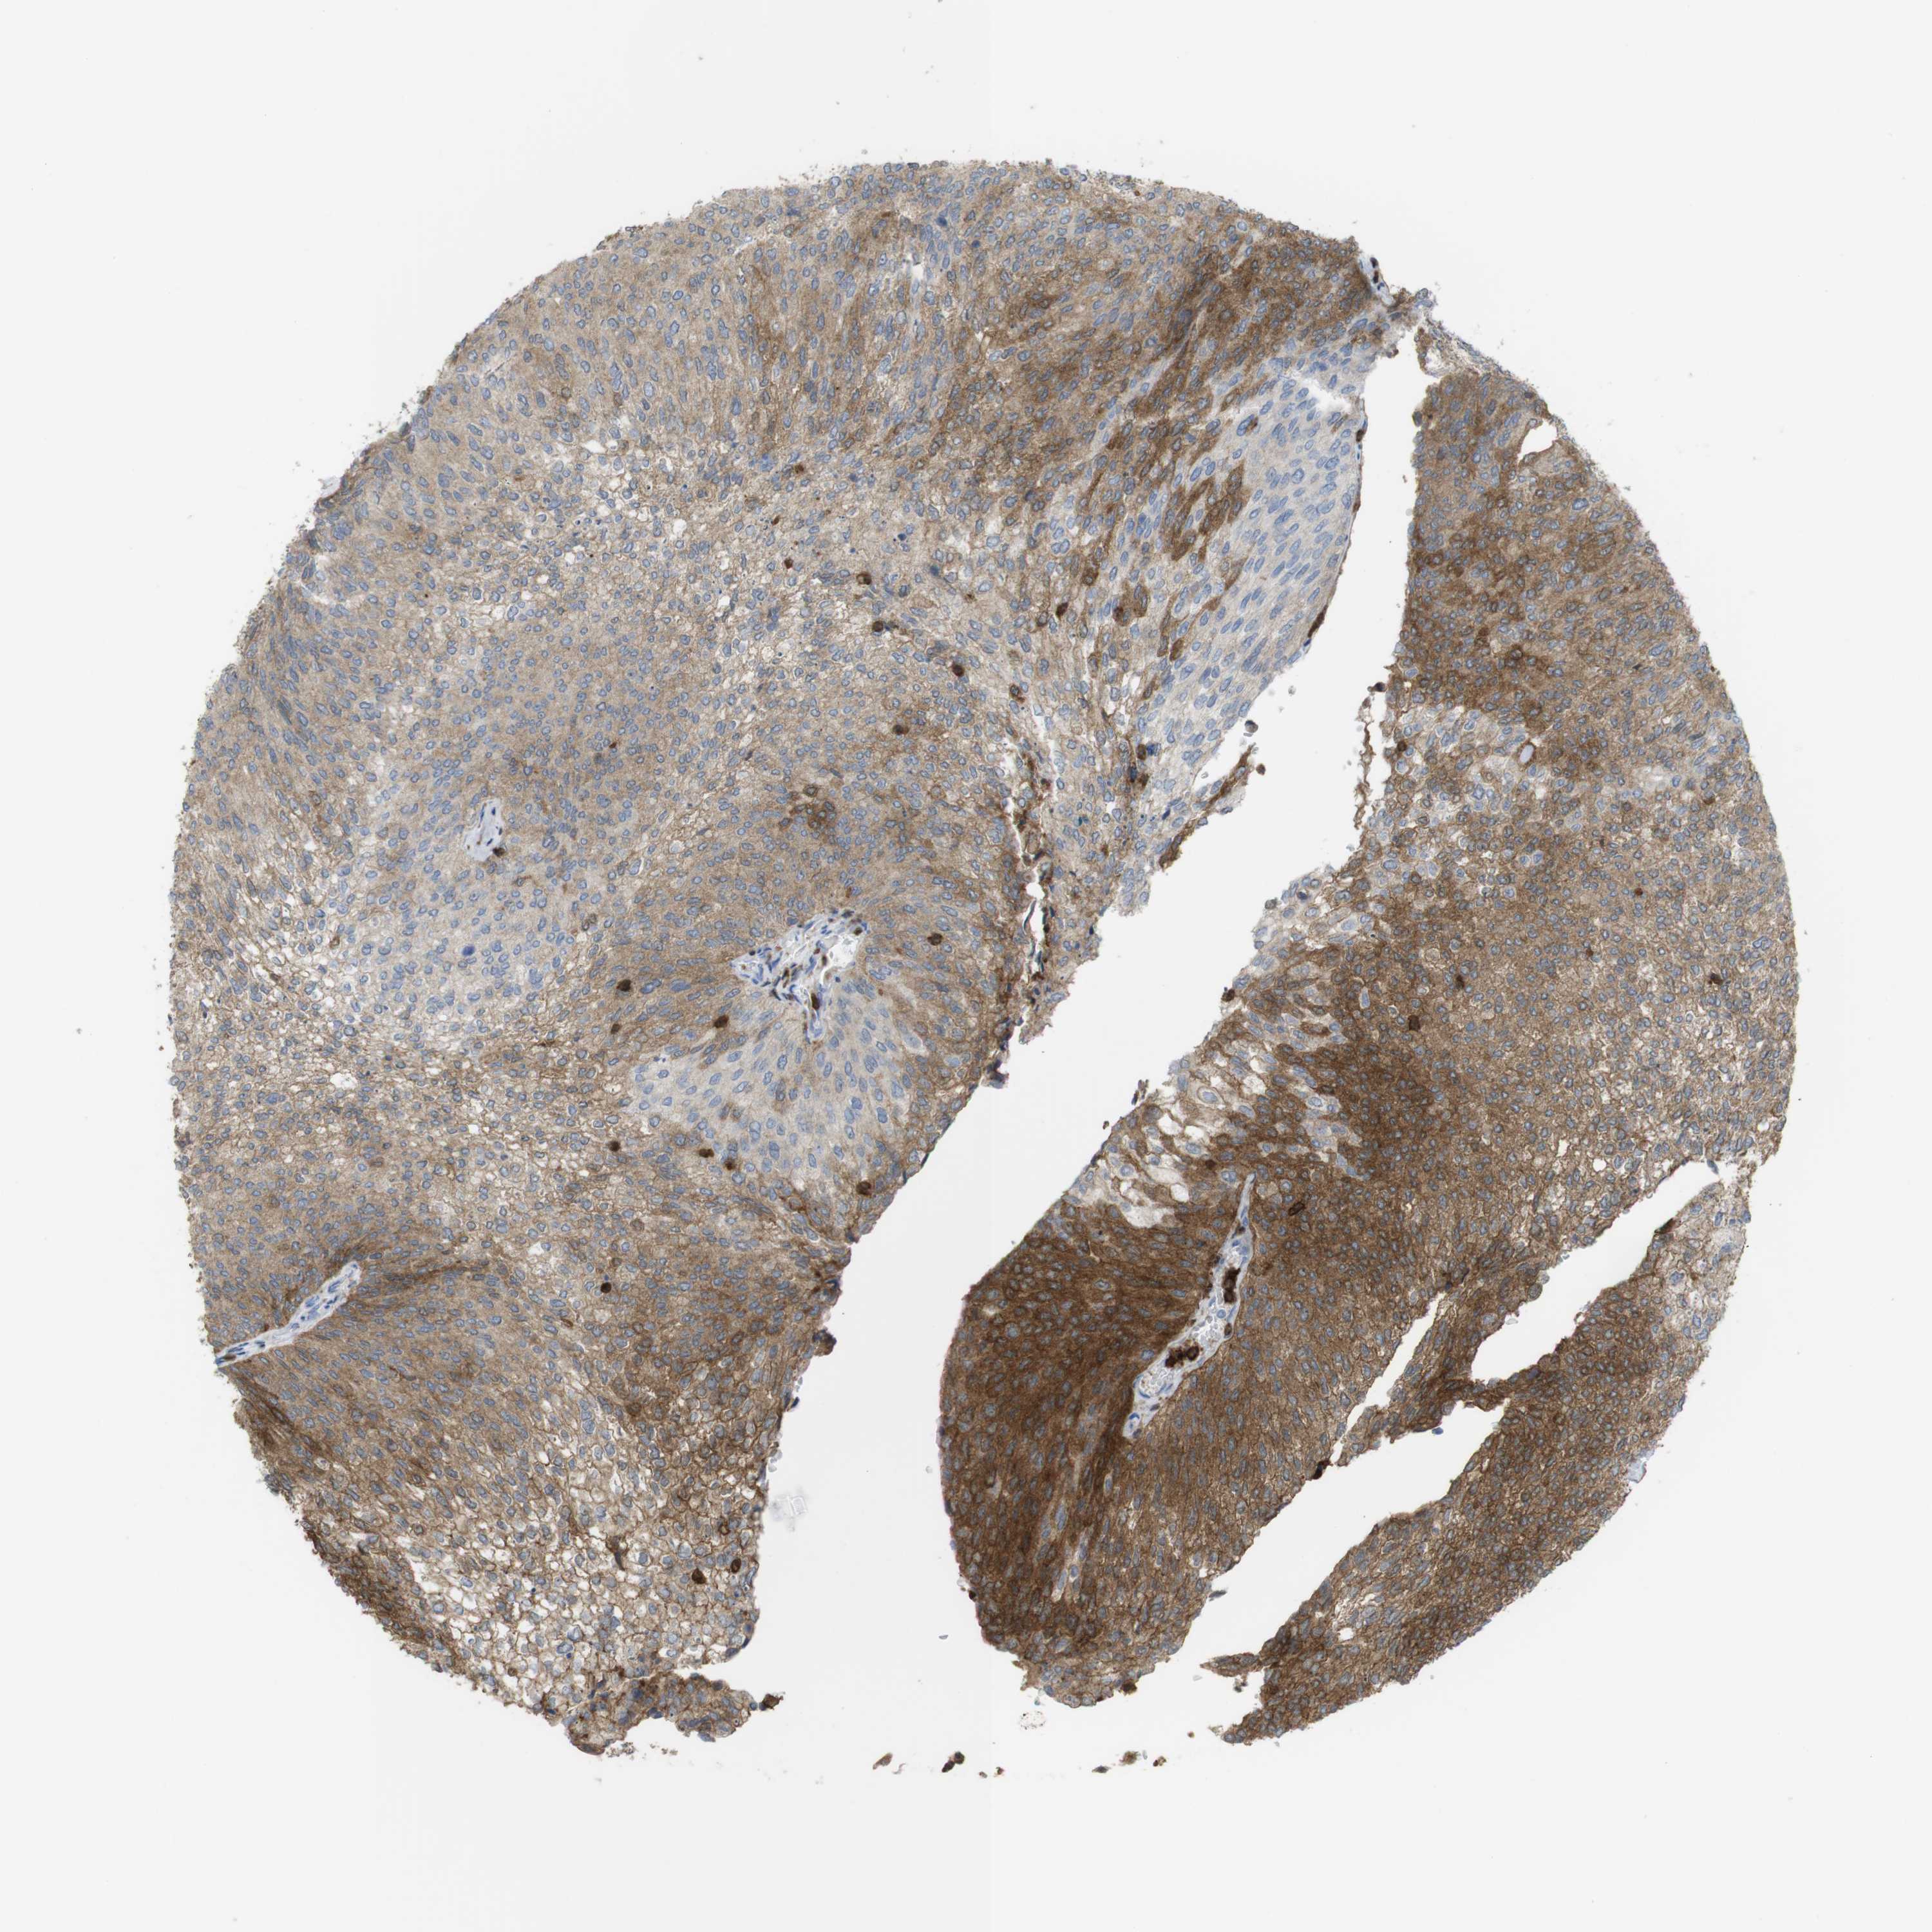

UROTHELIAL CANCER - Protein expressioni

A mouse-over function shows sample information and annotation data. Click on an image to view it in a full screen mode. Samples can be filtered based on level of antibody staining by selecting one or several of the following categories: high, medium, low and not detected. The assay and annotation is described here.

Antibody stainingi

Antibody staining in the annotated cell types in the current human tissue is reported as not detected, low, medium, or high, based on conventional immunohistochemistry profiling in selected tissues. This score is based on the combination of the staining intensity and fraction of stained cells.

Each image is clickable and will lead to virtual microscopy that enables deeper exploration of all samples and also displays staining intensity scores, fraction scores and subcellular localization as well as patient and tissue information for each sample.

Antibody HPA001863

Antibody HPA001890

Antibody CAB010469

Antibody CAB013225

Staining

High

Medium

Low

Not detected

Intensity

Strong

Moderate

Weak

Negative

Quantity

>75%

75%-25%

<25%

None

Location

Nuclear

Cytoplasmic/membranous

Cytoplasmic/membranous,nuclear

Urothelial carcinoma, High grade

Urothelial carcinoma, Low grade

Adenocarcinoma, NOS